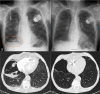

A wide spectrum of conditions, from life-threatening to non-urgent, can manifest with acute dyspnea, thus presenting major challenges for the treating physician when establishing the diagnosis and severity of the underlying disease. Imaging plays a decisive role in the assessment of acute dyspnea of cardiac and/or pulmonary origin. This article presents an overview of the current imaging modalities used to narrow the differential diagnosis in the assessment of acute dyspnea of cardiac or pulmonary origin. The current indications, findings, accuracy, and limits of each imaging modality are reported. Chest radiography is usually the primary imaging modality applied. There is a low radiation dose associated with this method, and it can assess the presence of fluid in the lung or pleura, consolidations, hyperinflation, pneumothorax, as well as heart enlargement. However, its low sensitivity limits the ability of the chest radiograph to accurately identify the causes of acute dyspnea. CT provides more detailed imaging of the cardiorespiratory system, and therefore, better sensitivity and specificity results, but it is accompanied by higher radiation exposure. Ultrasonography has the advantage of using no radiation, and is fast and feasible as a bedside test and appropriate for the assessment of unstable patients. However, patient-specific factors, such as body habitus, may limit its image quality and interpretability. Advances in knowledge This review provides guidance to the appropriate choice of imaging modalities in the diagnosis of patients with dyspnea of cardiac or pulmonary origin.